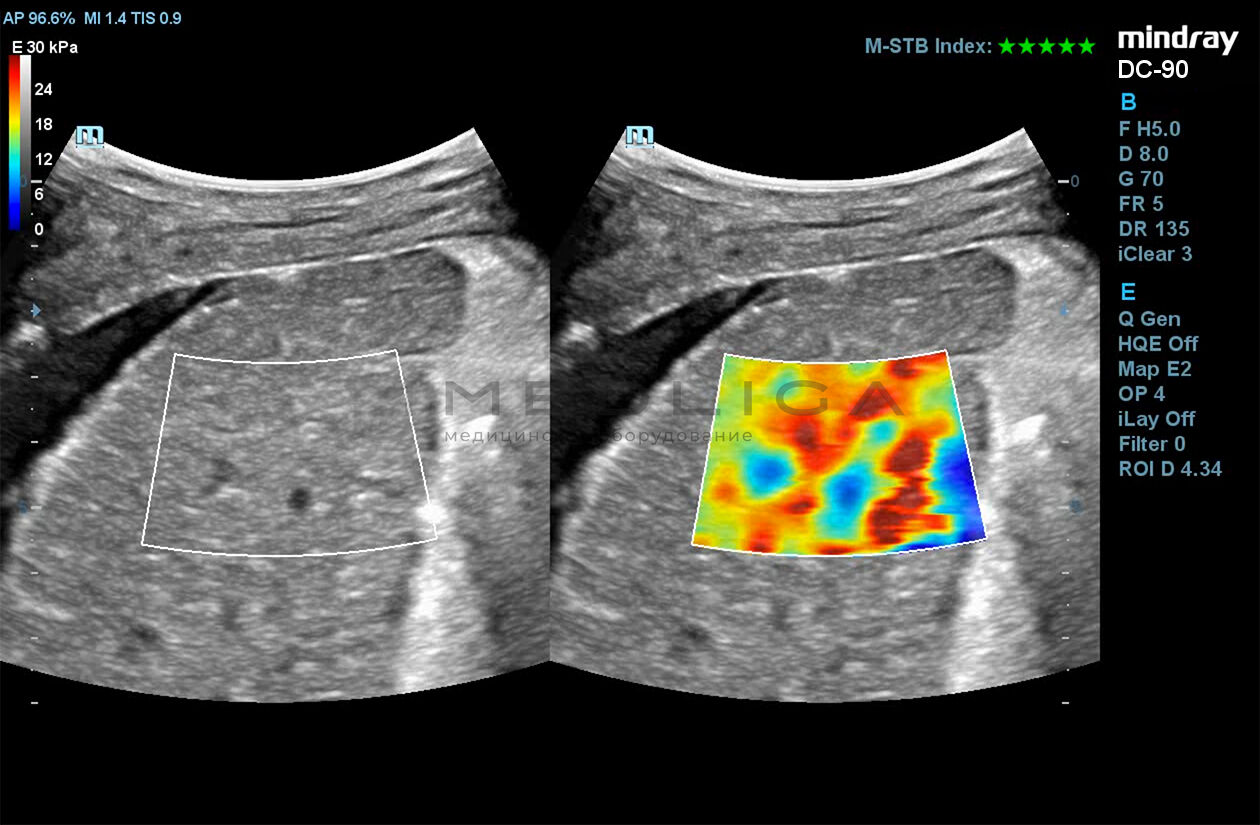

Программное обеспечение для оценки эластичности ткани методом эластографии сдвиговой волны (метод 2D-с формированием двухмерной цветовой эластограммы и количественной оценкой эластичности) на линейных и конвексных датчиках.

STE интегрирована с эксклюзивной технологией Ultra-Wide Beam Tracking от Mindray для двумерной эластографии сдвиговой волной в реальном времени. Специализированные измерительные инструменты позволяют проводить количественный анализ модуля упругости с высокой точностью.